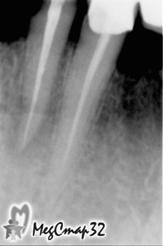

В первое посещение был снят протез, распломбирован ранее

некачественно запломбированный канал зуба

в очаг инфекции выведен противомикробный препарат (рис. 1).